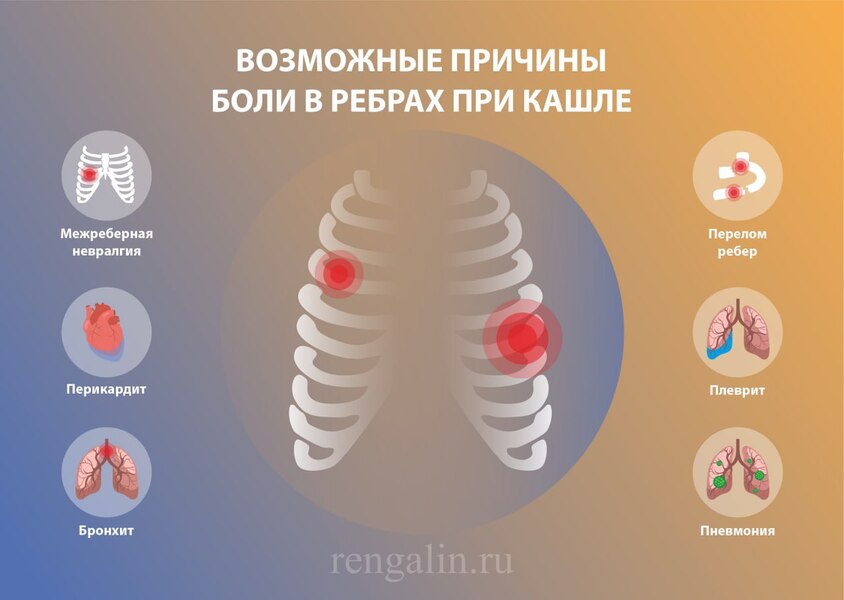

Причины и лечение боли в грудной клетке при кашле